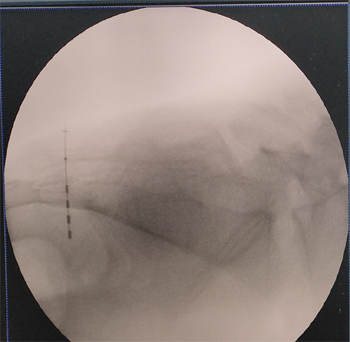

由于骶神经电调节手术是非常微创的手术,因此只需在局部麻醉下即可对患者施行手术。在骨科同事和外院专家的协助下,我们顺利将纤细的刺激电极置入患者的骶神经孔,并准确的将刺激电极贴附在骶神经上,随后电极与导线和刺激器相连接。手术进行了半个小时就顺利结束。1

术中C型臂定位穿刺